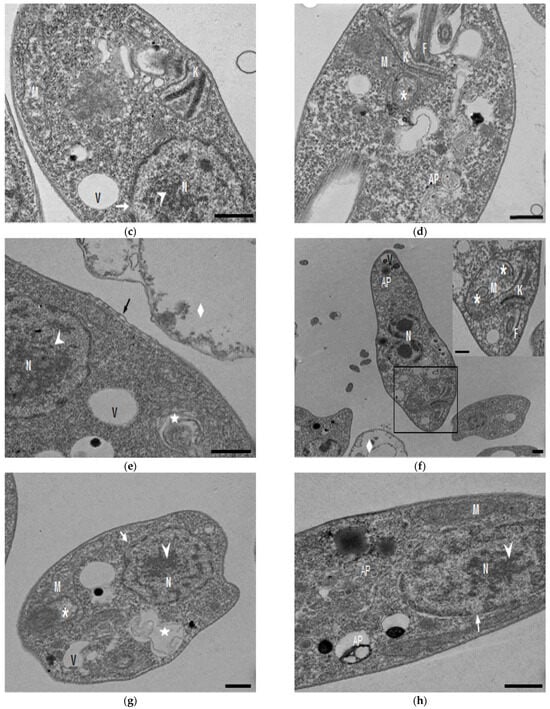

2.2. Transmission Electronic Microscopy

In the TEM studies (Figure 2), the control parasites were found to have plasma membranes and their characteristic structures without any damage (Figure 2a). However, the parasites treated for 6 h at 0.32 µM showed some early effects induced by compound 8 (Figure 2b–d). Some ultrastructural changes were evident such as the formation of autophagosomes and mitochondrion swelling with the presence of concentric membranal structures inside as well as an exocytic activity in the flagellar pocket, detachment of the flagellar membrane and alterations in the kinetoplast. Meanwhile, at 3.2 µM for 12 h (Figure 2e–h), the treated parasites showed even more profound changes such as the presence of increased vacuolization and autophagosomes, cytoplasmic myelin-like figures, plasma membrane detachment, rupture of the nuclear membrane and abnormal chromatin condensation. Total mitochondrion disorganization with swelling and concentrical membranes inside and, in some cases, the loss of cell integrity and cytosolic content were also observed.

Figure 2.

TEM analysis of L. mexicana promastigotes: non-treated (a) and treated with compound 8 at 0.32 µM 6 h (b–d) and 3.2 µM for 12 h (e–h). Control parasites show a normal morphology. Parasites treated with compound 8 show the presence of autophagosomes (APs) (d,f,h) and several alterations such as flagellar membrane detachment (black arrow) and exocytic activity in the flagellar pocket (black arrowhead) (b), kinetoplast structural alterations (c), mitochondrion swelling and concentric membranes inside (asterisks) (d,f,g), chromatin condensation (white arrowhead) (c,e,g,h), rupture of nuclear membrane (white arrow) (c,g,h), plasmatic membrane detachment (black arrow) (e) and cytoplasmic myelin figures (white stars) (e,g); loss of cell integrity and cytosolic content (white rhombus) (e,f); nucleus (N), mitochondrion (M), flagella (F), flagellar pocket (FP), kinetoplast (K), acidocalcisome (Ac), lipid body (LB), vacuole (V) (bar = 0.5 µm).

In the present study, with an interest in continuing the characterization of compound 8’s leishmanicidal activity, SEM studies were performed. It was demonstrated that compound 8 induced important ultrastructural changes in L. mexicana promastigotes such as membrane blebbing resembling an apoptotic-like process [20] and alterations in the flagella structure. In addition, TEM studies revealed alterations in the kinetoplast structure and profound mitochondrion damage including swelling and the presence of concentric membranes inside the organelle. We also observed cytoplasmic myelin-like figures indicative of an autophagy process, among other changes. Similar findings were described when L. amazonensis promastigotes were treated with Miltefosine [20], antifungal azoles [21] and calpains inhibitors [22]. In trypanosomastids, severe mitochondrion damage as well as an intense autophagy process and subsequent apoptosis cell death was related to a significant increase in reactive oxygen and nitrogen species (ROS and RNS) [23]. Parasites are exposed to extracellular ROS during their entire life cycle in the insect vector, as well as during the invasion of mammalian host cells [24], but ROS are also produced within the parasite through its electron transport chain or drug detoxification. In the present study, it was demonstrated that compound 8 triggers the production of ROS and parasite apoptosis, indicating that intracellular ROS production induced with compound 8 could be related to mitochondrial damage, as well as membrane blebbing and myelin-like figures observed in the SEM and TEM studies. Parasite apoptosis induced with compound 8 was demonstrated in the flow cytometry studies.